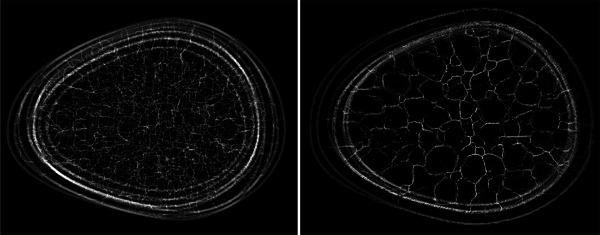

As part of this Grand Challenge, a common training dataset and an evaluation procedure was developed for benchmarking deep generative models for medical image synthesis. To create the training dataset, an established 3D virtual breast phantom was adapted. The resulting dataset comprised about 108 000 images of size 512   512. For the evaluation of submissions to the Challenge, an ensemble of 10 000 DGM-generated images from each submission was employed. The evaluation procedure consisted of two stages. In the first stage, a preliminary check for memorization and image quality (via the Fréchet Inception Distance [FID]) was performed. Submissions that passed the first stage were then evaluated for the reproducibility of image statistics corresponding to several feature families including texture, morphology, image moments, fractal statistics, and skeleton statistics. A summary measure in this feature space was employed to rank the submissions. Additional analyses of submissions was performed to assess DGM performance specific to individual feature families, the four classes in the training data, and also to identify various artifacts.

作为本次大挑战的一部分,开发了一个通用训练数据集和一个评估程序,用于对医学图像合成的深度生成模型进行基准测试。为了创建训练数据集,对一个已建立的3D虚拟乳房模型进行了改编。生成的数据集包含约108000张大小为512×512的图像。为了评估挑战赛的参赛作品,使用了来自每个参赛作品的10000张由深度生成模型生成的图像组成的集合。评估程序包括两个阶段。在第一阶段,进行了记忆和图像质量的初步检查(通过弗雷歇因距离 [FID])。通过第一阶段的参赛作品随后被评估与包括纹理、形态、图像矩、分形统计和骨架统计在内的几个特征族对应的图像统计数据的可重复性。在这个特征空间中使用一个汇总度量对参赛作品进行排名。对参赛作品进行了额外分析,以评估特定于各个特征族、训练数据中的四个类别的深度生成模型性能,还识别各种伪像。